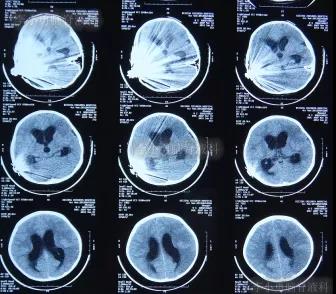

在利奈唑胺、头孢吡肟、利福平等药物抗炎治疗2周后,发热症状逐渐得到控制,意识也开始转清醒,但患儿自己示意有头痛症状;因腰穿未能抽出脑脊液,所以给予甘露醇处理,之后头痛可有缓解。在住院11天时即2012年5月27日(图-4)和住院14天时即2012年6月1日(图-5),分别进行过脑CT的检查,显示脑室有逐渐扩大的表现,但因为病情有所缓解,所以给以继续密切观察的处理。

图-4:2012年5月27日脑CT脑室稍扩大

图-5:2012年6月1日脑CT脑室稍扩大